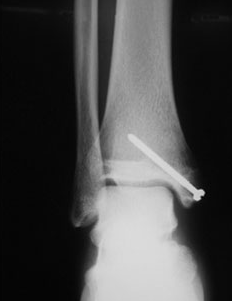

1. 내과 골절

발의 관절이 안쪽으로 강하게 뒤틀어지면 발목과 연결된 거골에 밀려 내과골절이 발생할 수 있고, 뼈가 어긋남 없이 골절되었다면 깁스 등의 보존적 치료등을 하게 됩니다. 하지만, 골절부위가 어긋난 버린 상태라면 스크루핀 등으로 고정하는 수술을 할 가능성이 있습니다.